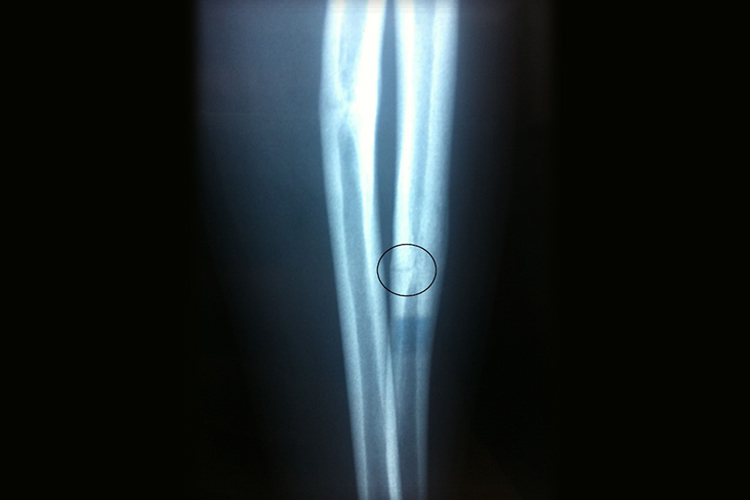

手臂轻微骨裂的症状主要表现为局部剧烈疼痛、肿胀,并在活动时疼痛加剧,伴有明显压痛,而且在骨裂处可形成皮下瘀斑或血肿,颜色可呈紫色、青色或黄色。需要通过X线、CT等影像学检查,明确手臂骨骼部位有相对不太清晰的骨折线。